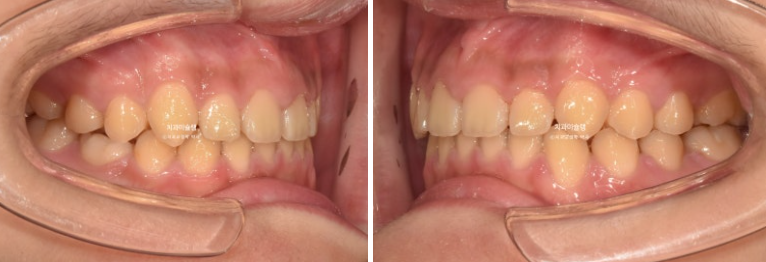

2년 전 교정치료를 위해 온 만 10세 어린이 입니다.

앞니가 하나 들려있고 깊게 물리는 과개교합이 있습니다.

중심선 불일치도 보입니다.

윗니 돌출이 측면에서 잘 보이네요.

영구치날 공간은 비교적 양호한 편입니다.